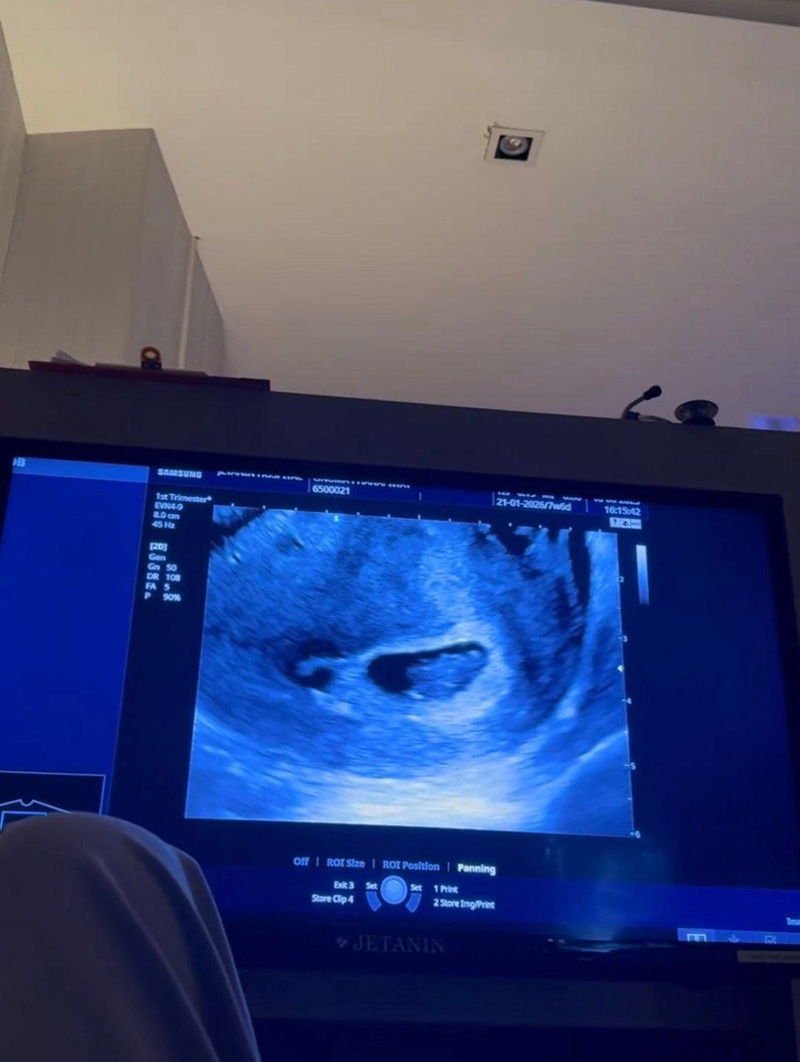

ล่าสุด (10 มิถุนายน 2568) หมออร อรอุมา กับ พี่ชิน ก็ได้ประกาศอีก 1 ข่าวดี คือกำลังจะมีลูกด้วยกันแล้ว หลังหมออรตั้งครรภ์ โดยได้เผยภาพคู่ของว่าที่คุณพ่อคุณแม่ โชว์รูปอัลตราซาวด์ของลูกน้อยในท้อง พร้อมข้อความว่า "เพราะเธอคือ สิ่งเล็ก ๆ ที่ฉันเรียกมันว่า … ความรัก #ขอบคุณที่แข็งแรงยอมให้แม่ทำงานหนักนะลูก"